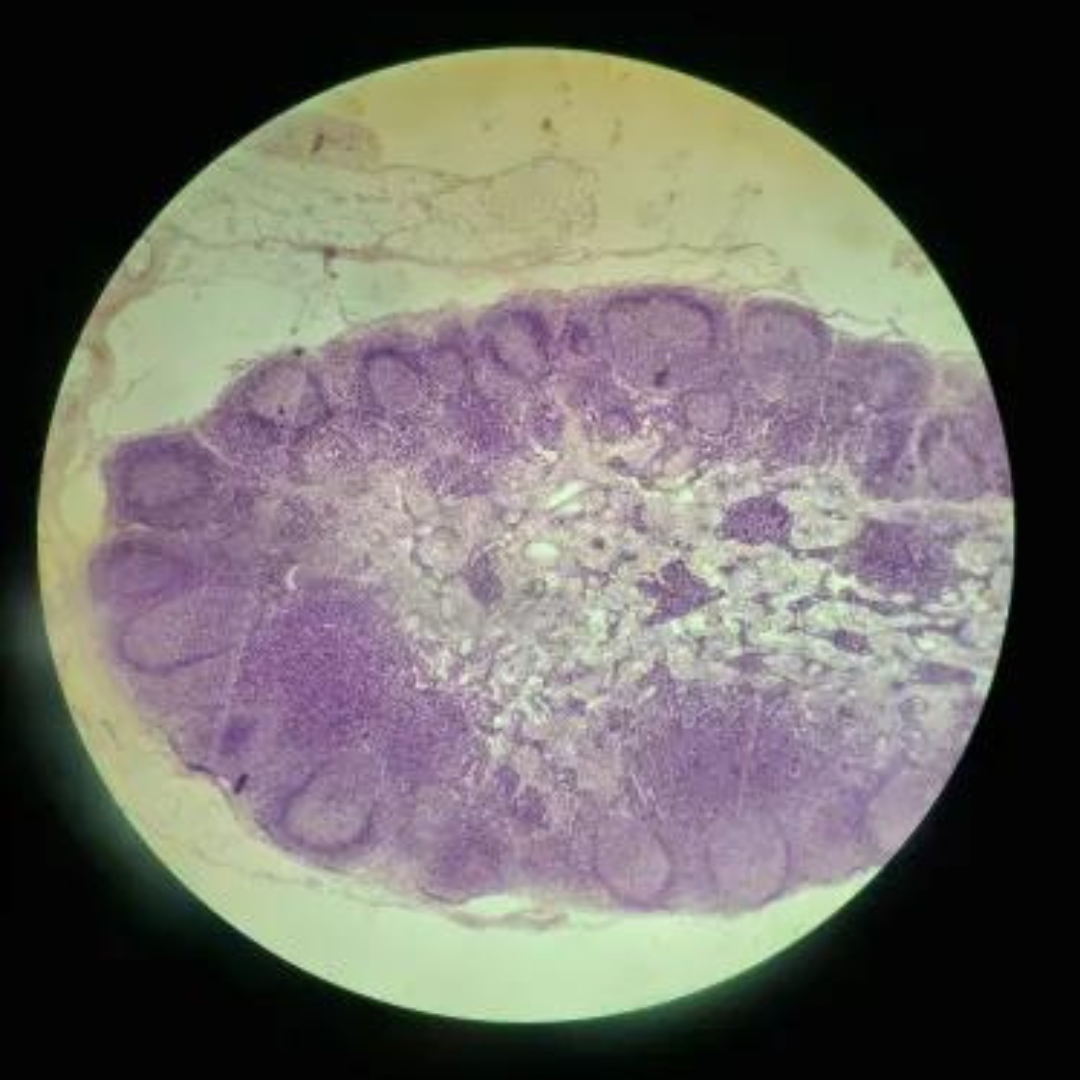

16

New cards

Tonsil

17

New cards

Tonsil

18

New cards

Tonsil

19

New cards

Tonsil